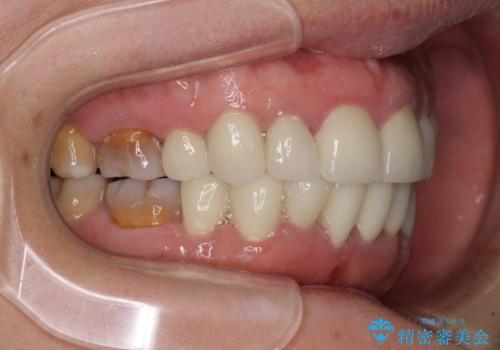

- 小さいころからの歯の変色と矯正治療の後戻りを気にして来院された患者様です。

気になる変色歯を仮歯に変え、その後歯列不正を矯正治療で改善し、最後にオールセラミッククラウンにて補綴治療することとしました。